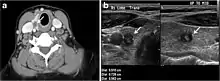

Fig. 7. A 51-year-old female patient post total thyroidectomy for PTC with elevated thyroglobulin measurement. an Axial non-enhanced CT scan of the neck at the level of the thyroid bed demonstrates a well-defined, rounded, homogenously dense soft tissue situated between the trachea and left internal jugular vein (white arrow). b Transverse ultrasound image of the neck demonstrates a well-defined, homogeneous, hypoechoic soft tissue nodule measuring 6 mm (white arrow) with no detected micro-calcifications. Biopsy showed a predominantly residual normal thyroid tissue with micro-foci of PTC.[1]